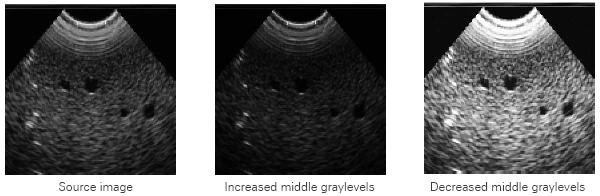

Gamma

Gamma increases or decreases the middle graylevels. In other words, you compensate the non-linear behavior of picture tubes: